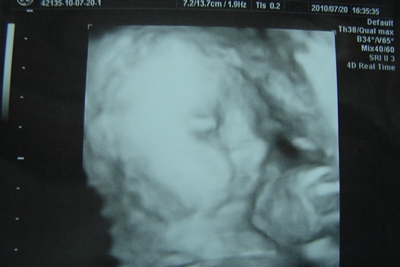

Rabbe: kaptam képet, de nem nagyon látszódik rajta, nem sikerült jó képet csinálnia a dokinőnek, mert a végén már megunta a leskelődést és hátat fordított.